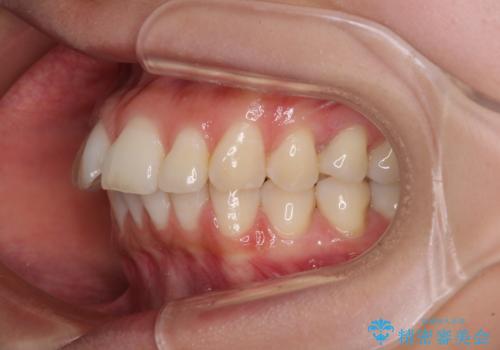

- 口を閉じたときに唇の間から飛び出してくる前歯を気にして来院された患者様です。

骨格的に上顎骨が前方位にあるため、左右の第一小臼歯を抜歯し、ワイヤー装置にて咬み合わせを整えていくこととしました。

前歯の突出感が改善されるだけでなく、奥歯の咬み合わせも改善され、食いしばりをしにくい状態に仕上げることができました。